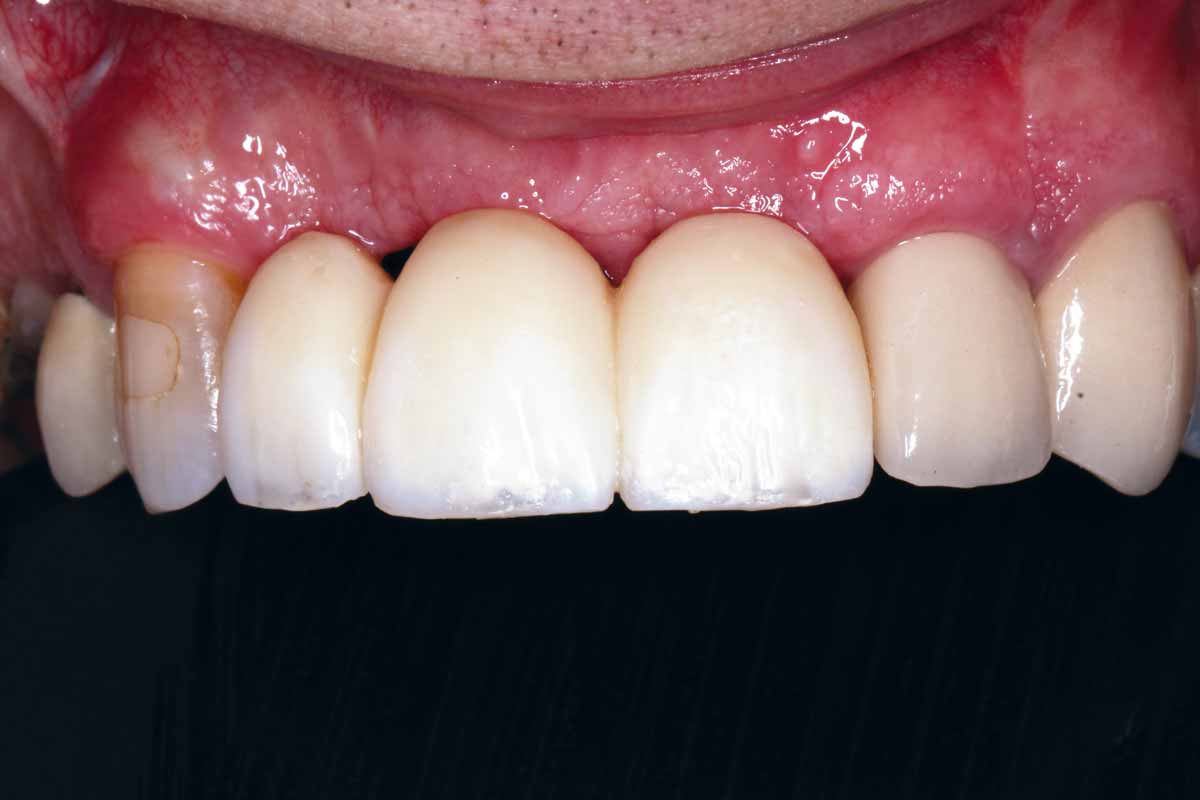

Implant placement and horizontal GBR in the aesthetic zone

Dr. Stavros Pelekanos – Greece